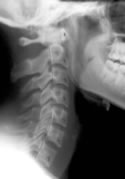

Identifying these ligamentous injuries, however, can be difficult. The ligaments themselves may be detected on MRI, but they cannot be seen on normal radiographs. It is more likely that the ligament injury will result in changes to the alignment of the cervical spine, and that can be detected with plain films.

A 2002 study1 compared the angle of cervical lordosis between whiplash patients and healthy controls. They found a statistically significant difference between the two groups, suggesting that whiplash injuries may indeed alter cervical spine alignment.

The authors of this current study began with 13 patients who had been in a car crash. They obtained a neutral cervical radiograph taken in the natural standing position. Then, each patient was treated by a chiropractor. The patients had an average age of 24, and the average number of chiropractic adjustments was 17.7.

After a period of care, neutral radiographs were again taken, and both the pre- and post-treatment films were evaluated by a second chiropractor who was blinded to which films belonged to which patient.

The cervical curve was measured in each of the x-rays.

10 of the 13 patients showed an increase in the cervical lordosis found on x-ray. The average increase found in the patients was 6.4°.

One patient showed no change and two patients showed a decrease in cervical lordosis.